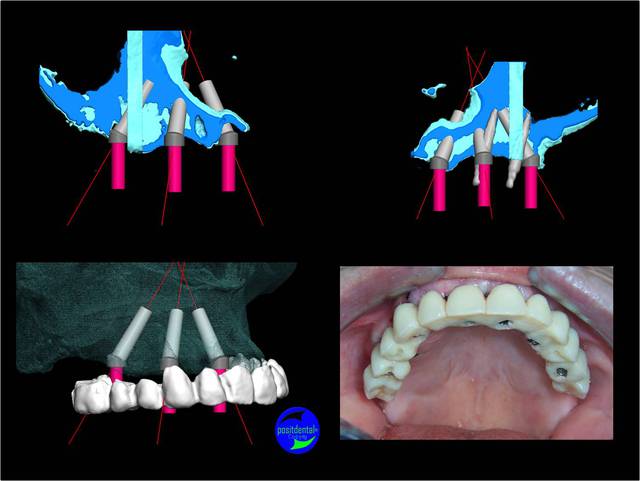

Zurg, la difficulté est de suivre la planification avec l’angulation prévu pour longer les sinus. Castor fait un tracé sur le maxillaire après ouverture d’une légère fenêtre et se sers d’un drapeau. Je suppose qu’il place un multi-unit pour vérifier l’indexation de l’implant. Il ne fait pas appel à sa seule visualisation mentale de l’espace. D’autres te parlent de sens clinique, avec les mots il est possible d’écrire beaucoup de chose mais comme le montre l’étude sur tête fantôme de VERMULEN même des praticiens expérimentés dévient de l’axe prévu et ce pour une unitaire avec des dents pour repères spatiaux.

Castor la position de l’apex de l’implant angulé est aussi importante pour laisser un volume osseux pour les implants mésiaux. Sur cet exemple il était important de le placer pré de la corticale palatine vestibulaire.la densité rencontrait fait que tu n’as spécialement une corticale sur laquelle t’appuyer.

Tu peux voir que les angulations planifiées sont correctement reproduites.